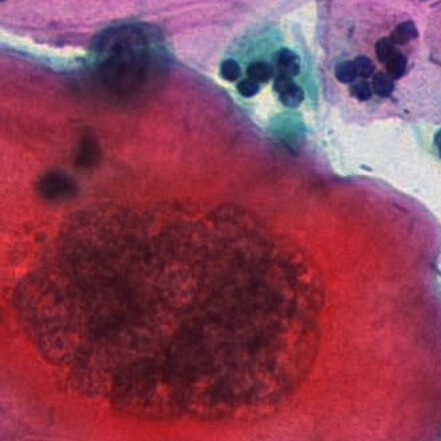

がん検診の際、生検やリキッドバイオプシーによって採取された検体には、腫瘍から剥離した細胞や腫瘍に関連するDNAが含まれることがあります。医師は、細胞の独自の特性に基づいて、正常な細胞か異常な細胞かを判断し、細胞病理学の程度を参考にして予後やその後の治療を決定します。

生検画像と細胞の変異

細胞の特性を分析することで、正常細胞とがん細胞を区別し、がん細胞を分類することができます。しかし、顕微鏡画像ではがん細胞は外観が異なり、ランダムに配置されているため、医師の判断や選択基準に大きな影響を与える可能性があります。これらの不確実性を考慮すると、従来の検査システムでは細胞の変異を検出し、判断するには不十分です。

正常細胞

中期病変